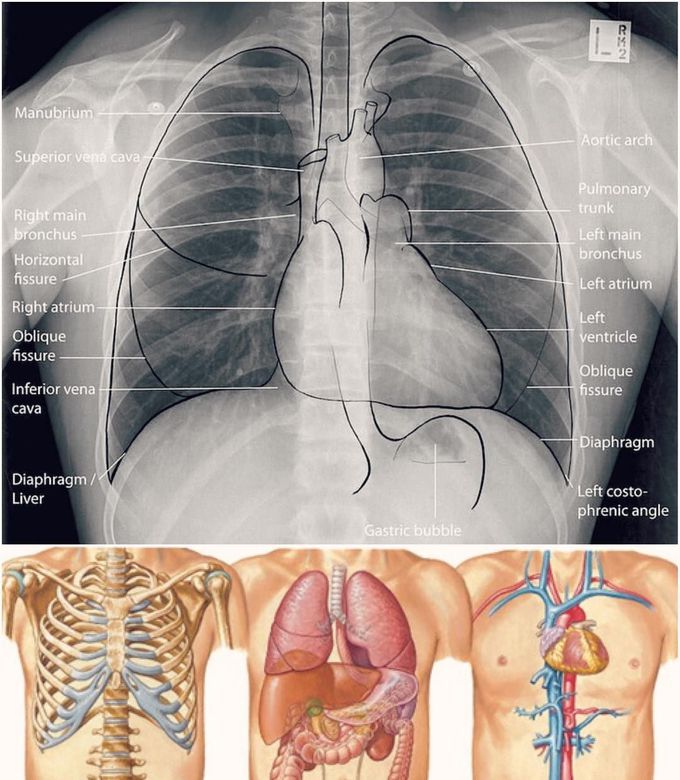

Magnetic resonance imaging (mri) utilizes magnet and radio waves to produce diagnostic images. Use the mouse scroll wheel to move the images up and down alternatively use the tiny arrows (>>) on both side of the image to move the images.>>) on both side of the image to move the images. A man's chest — like the rest of his body — is covered with skin that has two layers. Anatomical structures are labeled, providing an invaluable teaching. See chest anatomy stock video clips. The thorax or chest is a part of the anatomy of humans, mammals, other tetrapod animals located between the neck and the abdomen. The first step in understanding thorax anatomy is to find out its boundaries. Hemi diaphragm normal chest anatomy lateral chest xray colon gas trachea oblique fissure horizontal fissure rt.

Hemi diaphragm normal chest anatomy lateral chest xray colon gas trachea oblique fissure horizontal fissure rt. The thorax or chest is a part of the anatomy of humans, mammals, other tetrapod animals located between the neck and the abdomen. Anatomy of the chest and the lungs: About the 6th week, the somites differentiate into the sclerotomes and the dermatomyotomes. See chest anatomy stock video clips. As a result of differences in patient age, body habitus, positioning, inspiratory effort, exam technique, and many other factors, normal anatomic structures will vary in appearance on chest radiographs from exam to exam, patient to patient, and even breath to breath. Computed tomography (ct) of the chest can detect pathology that may not show up on a conventional chest radiograph(1). Great prices on anatomy of heart. Magnetic resonance imaging (mri) utilizes magnet and radio waves to produce diagnostic images. Anatomical structures are labeled, providing an invaluable teaching. This page provides an overview of the chest muscle group. Man head and chest anatomy diagram with ghost effect. It provides protection to vital organs (eg, heart and major vessels, lungs, liver) and provides stability for movement.